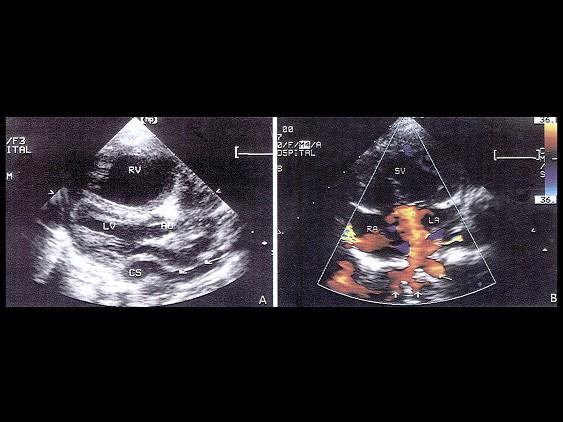

该病例最可能的诊断?(?)A.肺静脉畸形引流入右心房B.肺静脉畸形引流入冠状窦C.肺静脉畸形引流入上腔D.肺静脉畸形引流入下腔E.以上都不是

选项 A.肺静脉畸形引流入右心房 B.肺静脉畸形引流入冠状窦 C.肺静脉畸形引流入上腔 D.肺静脉畸形引流入下腔 E.以上都不是

答案 B